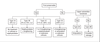

What is the management of developmental coxa vara?

[Lovell and Winter]

- Nonoperative

- H-E angle <45

- H-E angle 45-59 and asymptomatic

2.Operative

- H-E angle >60

- H-E angle 45-59 and symptomatic

- Symptomatic limp, Trendelenburg gait, or progressive deformity

- Neck shaft angle <100

- Technique:

- Valgus-producing proximal femoral osteotomy

What is the goal of correction in developmental coxa vara?

- <38° H-E angle [Orthobullets]

- 16° H-E angle [Lovell and Winter]